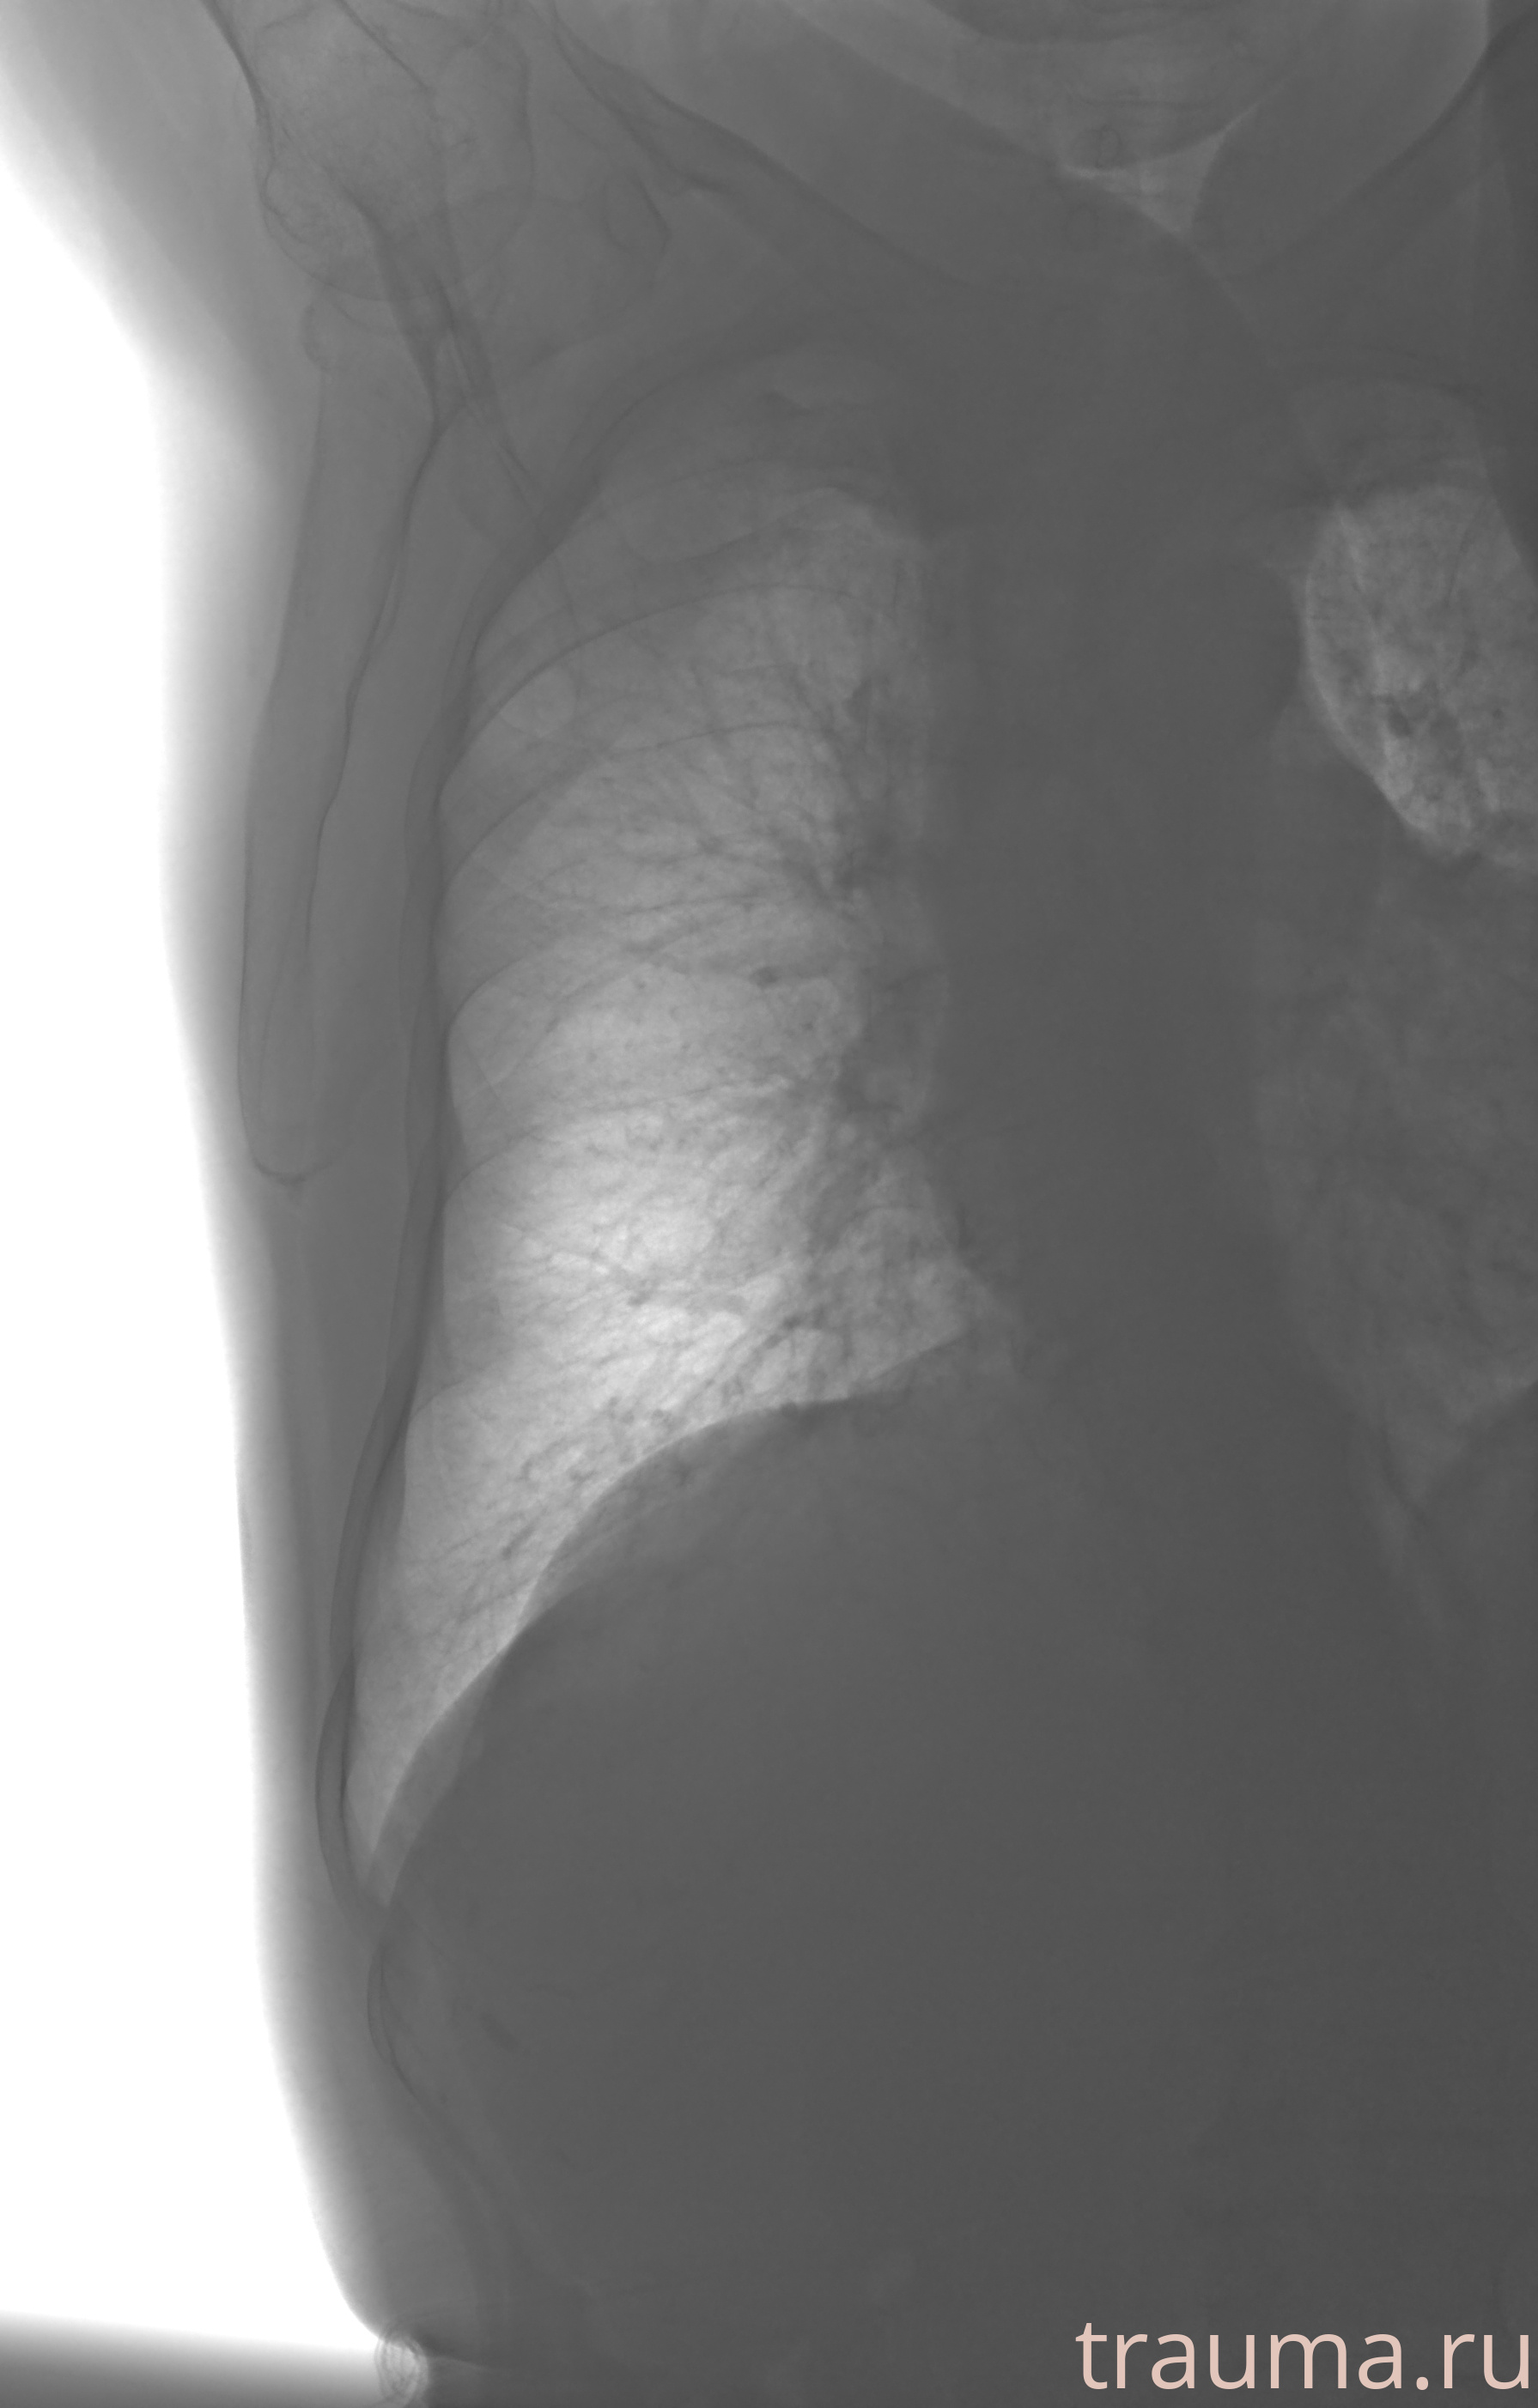

Рентген на дому: по вашему адресу приезжает врач-рентгенолог, травматолог-ортопед с мобильным рентгеновским аппаратом, проводит диагностику травмы или заболевания, делает необходимые рентгенограммы, дает рекомендации по дальнейшему лечению. Получить качественные снимки в домашних условиях возможно благодаря уникальной методике, разработанной МосРентген Центром для института  Склифосовского